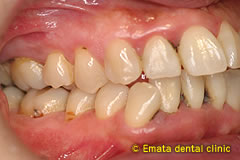

根分岐部病変

(根が分岐している奥歯に生じた歯周病)

の治療

~専門医・指導医による歯周病治療3~

治療の概要

根分岐部病変は、歯根が2本以上ある歯の根分岐部まで進行した歯周病で、歯石除去が難しくブラッシングもしにくい場所のため、症状が出にくく治療が難しいのが特徴です。歯周病を制するには根分岐部病変を制する必要があり、進行した場合は抜歯の選択肢が検討されることも少なくありません。

治療の流れ

-

01

スケーリング・ルートプレーニング

02

歯根分割・抜根・エムドゲイン

03

歯根分割・抜根・トンネリング・抜歯

さっさと抜いてインプラント、ではなく、根分岐部病変をどう考えてどう生かすかが歯周病専門医の姿勢や力量です。

治療例の紹介